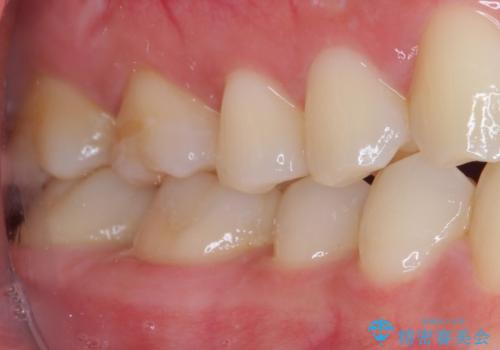

銀歯をセラミックにしたい セラミックインレー修復

- 銀歯をセラミックにしたいとのことで来院された患者様です。

まず麻酔をして銀歯を外し、むし歯を除去し、形を整えて型取りします。

そして次の来院時、セラミックインレーを装着し、噛み合わせなどの調整を行います。

それを左右に分けて行いました。

インレーを装着するときは、唾液や血液による接着力の低下を避けるためにラバーダム防湿を行いました。

自然な色調で大変満足されました。